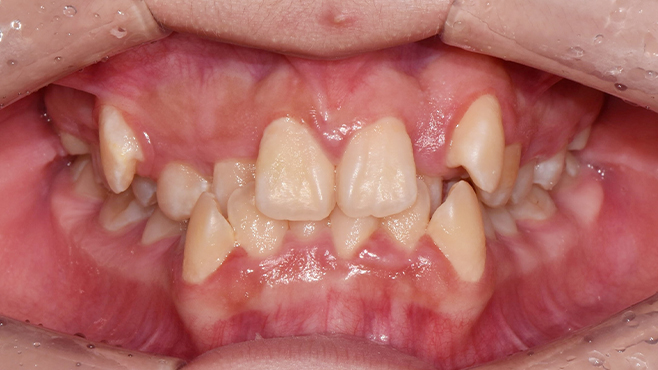

맞는 건 괜찮은데… 충치는 못 참겠습니다|20대 격투기 선수 치과 방문기

2026.02.06